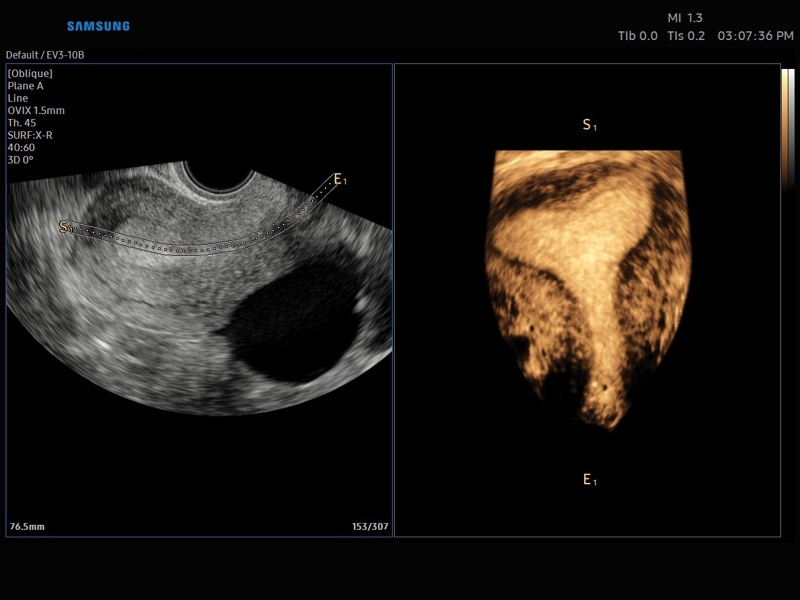

• Smart 4D с технологиями Realistic VUE и Crystal VUE

• 3D - трехмерное сканирование объемными датчиками в статическом режиме в серой шкале и восстановление объемной структуры сосудов в режиме цветного / энергетического допплера (необходим Static 3D).

• 4D - трехмерное сканирование объемными датчиками в реальном масштабе времени (необходима опция Smart 4D).

• Система Static 3D - трехмерное сканирование объемными датчиками в статическом режиме в серой шкале и восстановление объемной структуры сосудов в режиме цветного / энергетического допплера).

• СистемаLive 3D- трехмерное сканирование объемными датчиками в реальном масштабе времени (4D).

• OVIX(Oblique View eXtended) - получение фрагмента трехмерного изображения (в виде нескольких полупрозрачных сканов, последовательно наложенных один на другой) в направлении произвольного косого среза трехмерного объекта исследования.